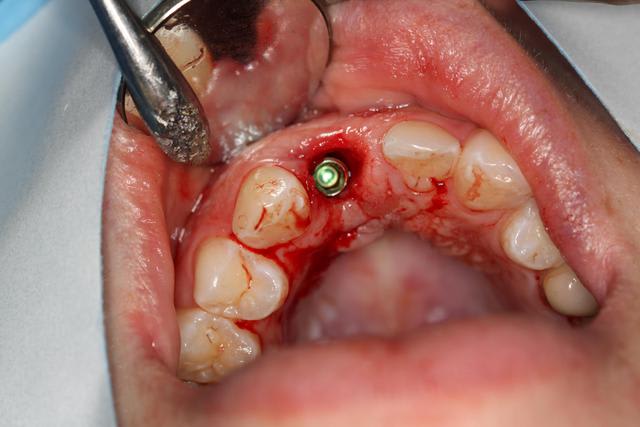

Implant posé ce matin

Le guide n'a pas été utilisé. Pas assez stable, délicat pour la visibilité, me sentais moins bien avec que sans : l'axe me paraissait pas correspondre, peur de fraiser de la résine.

Extraction simple, hauteur racine 10mm.

Alvéole propre, "boulevard" pour implanter.

Premier forage légerement en palatin, trop car petite excursion dans canal retro incisif.

Reprise de l'axe finalement au fond de l'alvéole.

Implant Legacy (ayé) 3 4,2x16mm

Bonne stabilité primaire, saignement abondant.

Utilisation pilier provisoire résine plateforme 4.7, injection de flow et polissage pour galber mais pas trop pour que la gencive revienne.

Pas de sutures, pas besoin.

Les critiques (productives et modérées) sont les bienvenues